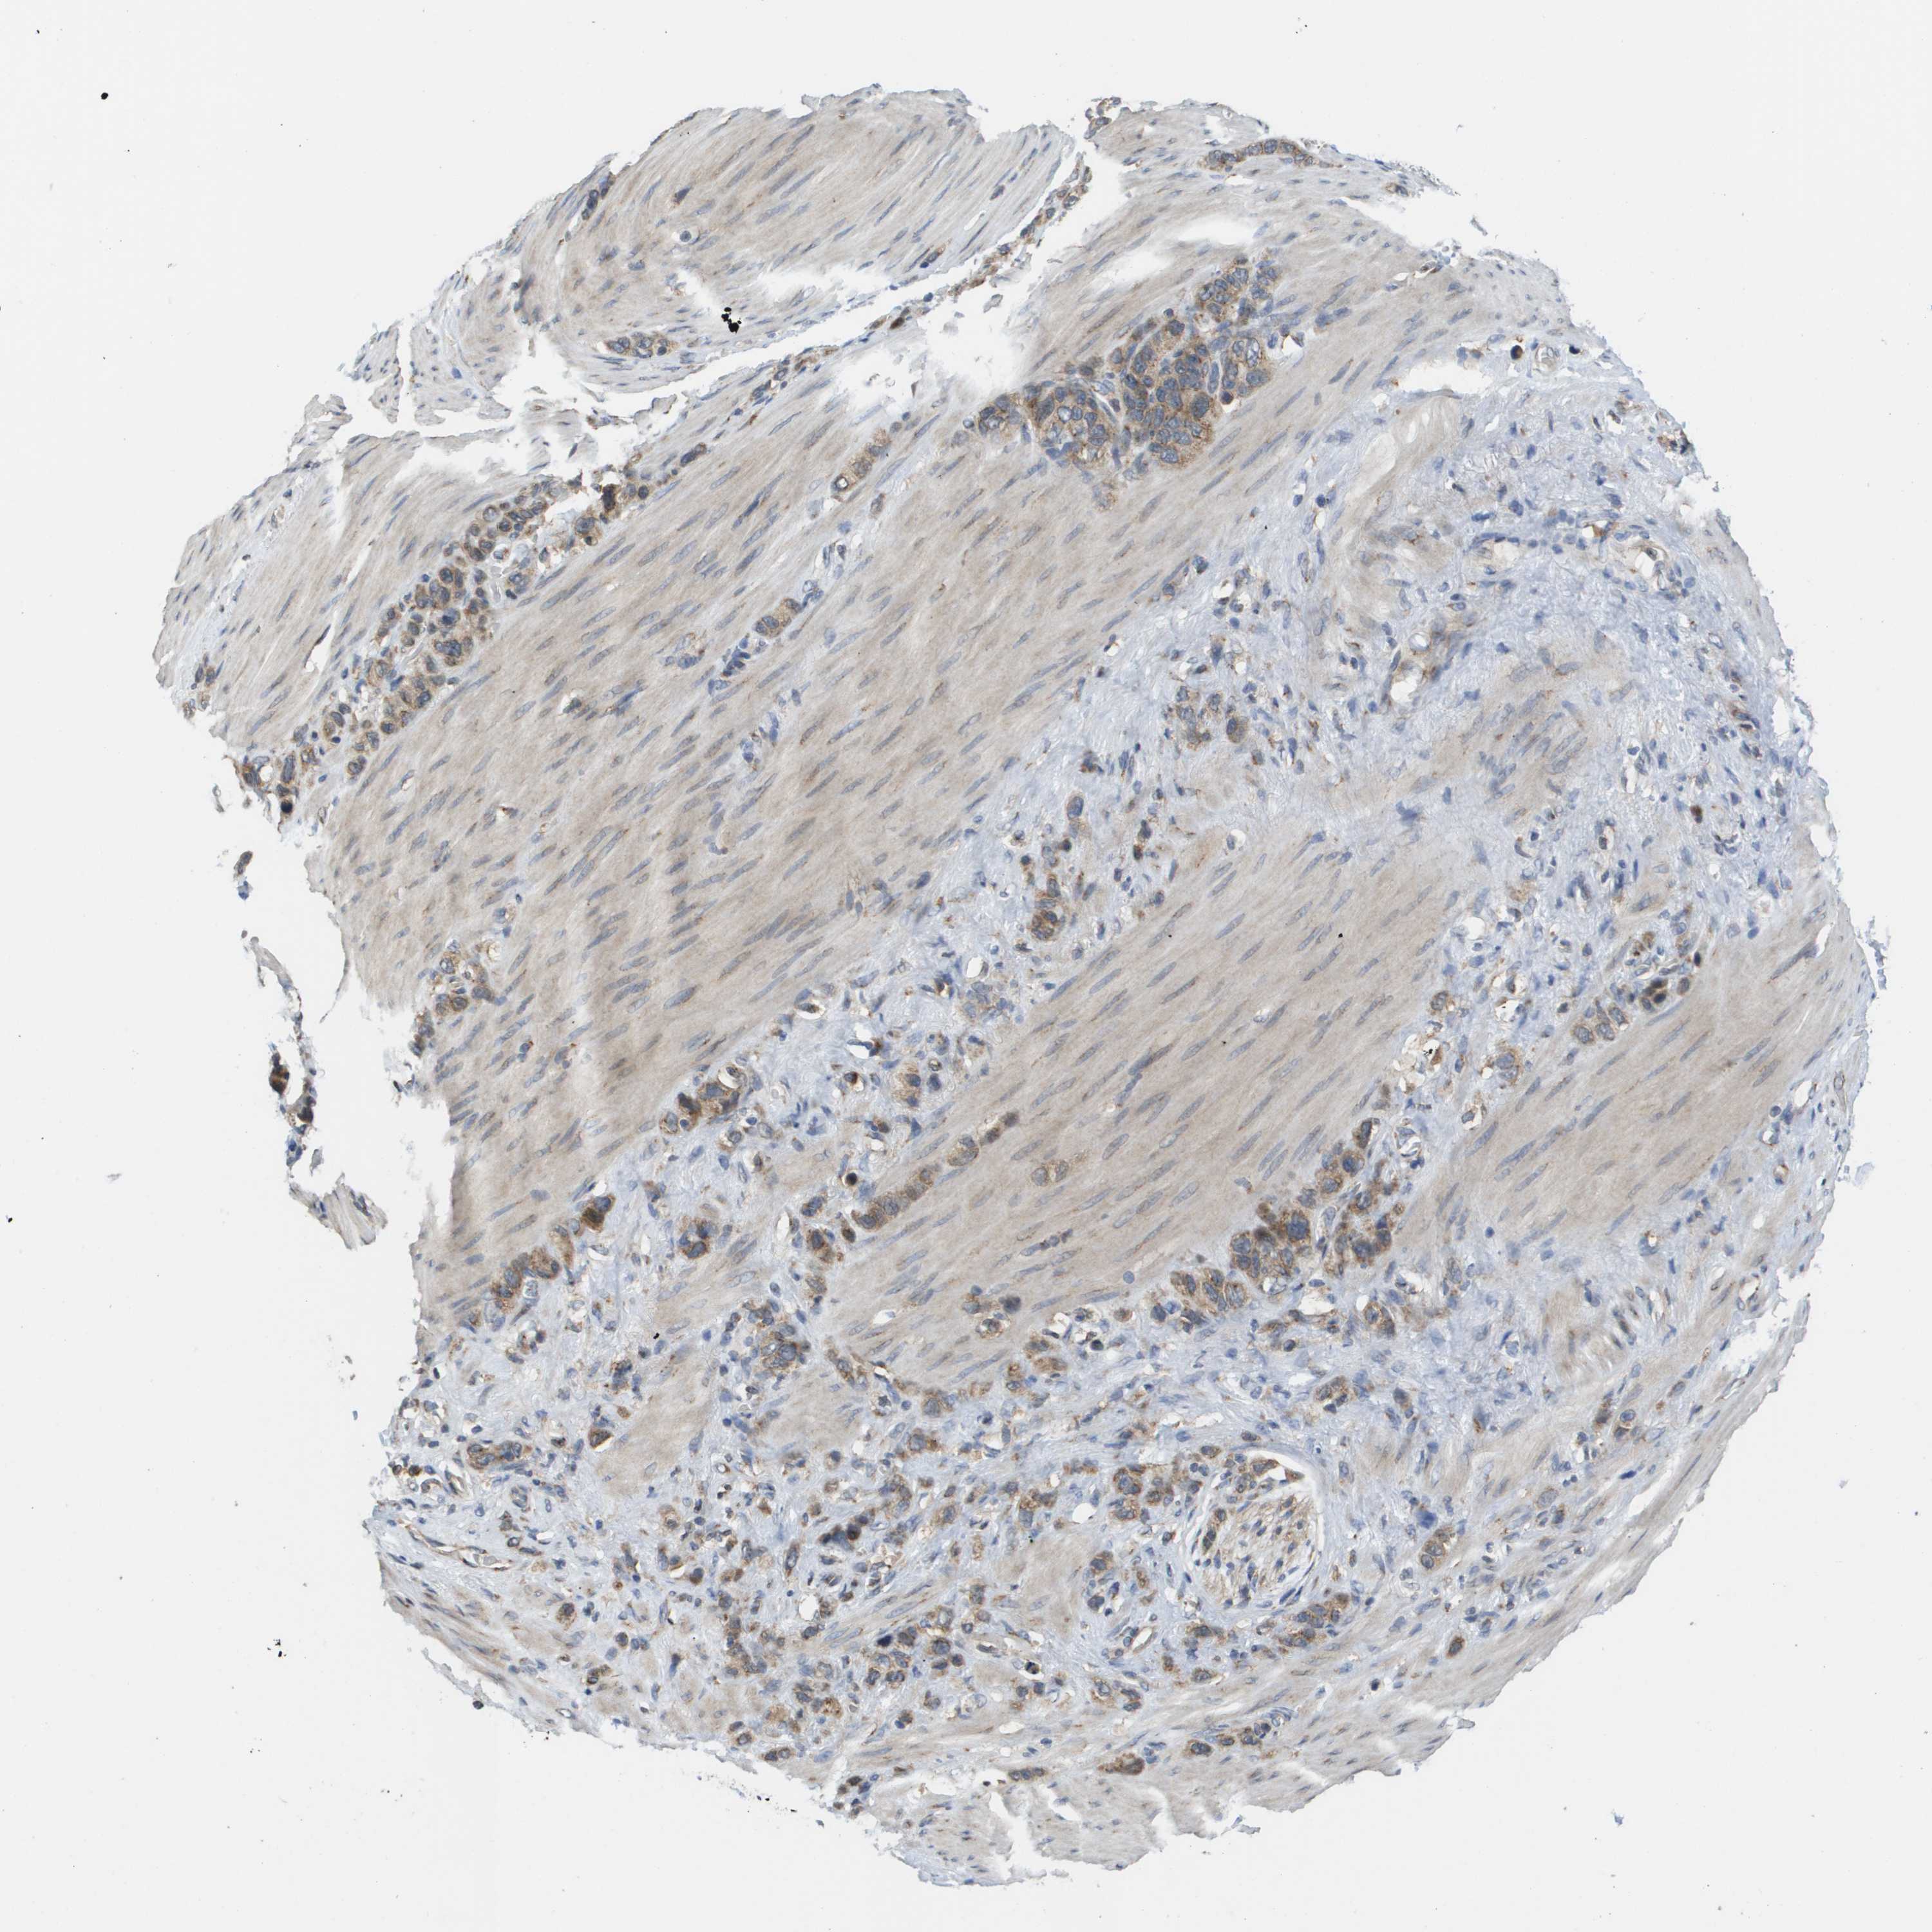

STOMACH CANCER - Protein expressioni

A mouse-over function shows sample information and annotation data. Click on an image to view it in a full screen mode. Samples can be filtered based on level of antibody staining by selecting one or several of the following categories: high, medium, low and not detected. The assay and annotation is described here.

Note that samples used for immunohistochemistry by the Human Protein Atlas do not correspond to samples in the TCGA dataset.

Antibody stainingi

Antibody staining in the annotated cell types in the current human tissue is reported as not detected, low, medium, or high, based on conventional immunohistochemistry profiling in selected tissues. This score is based on the combination of the staining intensity and fraction of stained cells.

Each image is clickable and will lead to virtual microscopy that enables deeper exploration of all samples and also displays staining intensity scores, fraction scores and subcellular localization as well as patient and tissue information for each sample.

Antibody HPA006277

Antibody HPA006507

Antibody CAB017027

Staining

High

Medium

Low

Not detected

Intensity

Strong

Moderate

Weak

Negative

Quantity

>75%

75%-25%

<25%

None

Location

Nuclear

Cytoplasmic/membranous

Cytoplasmic/membranous,nuclear

Adenocarcinoma, NOS

Adenocarcinoma, High grade